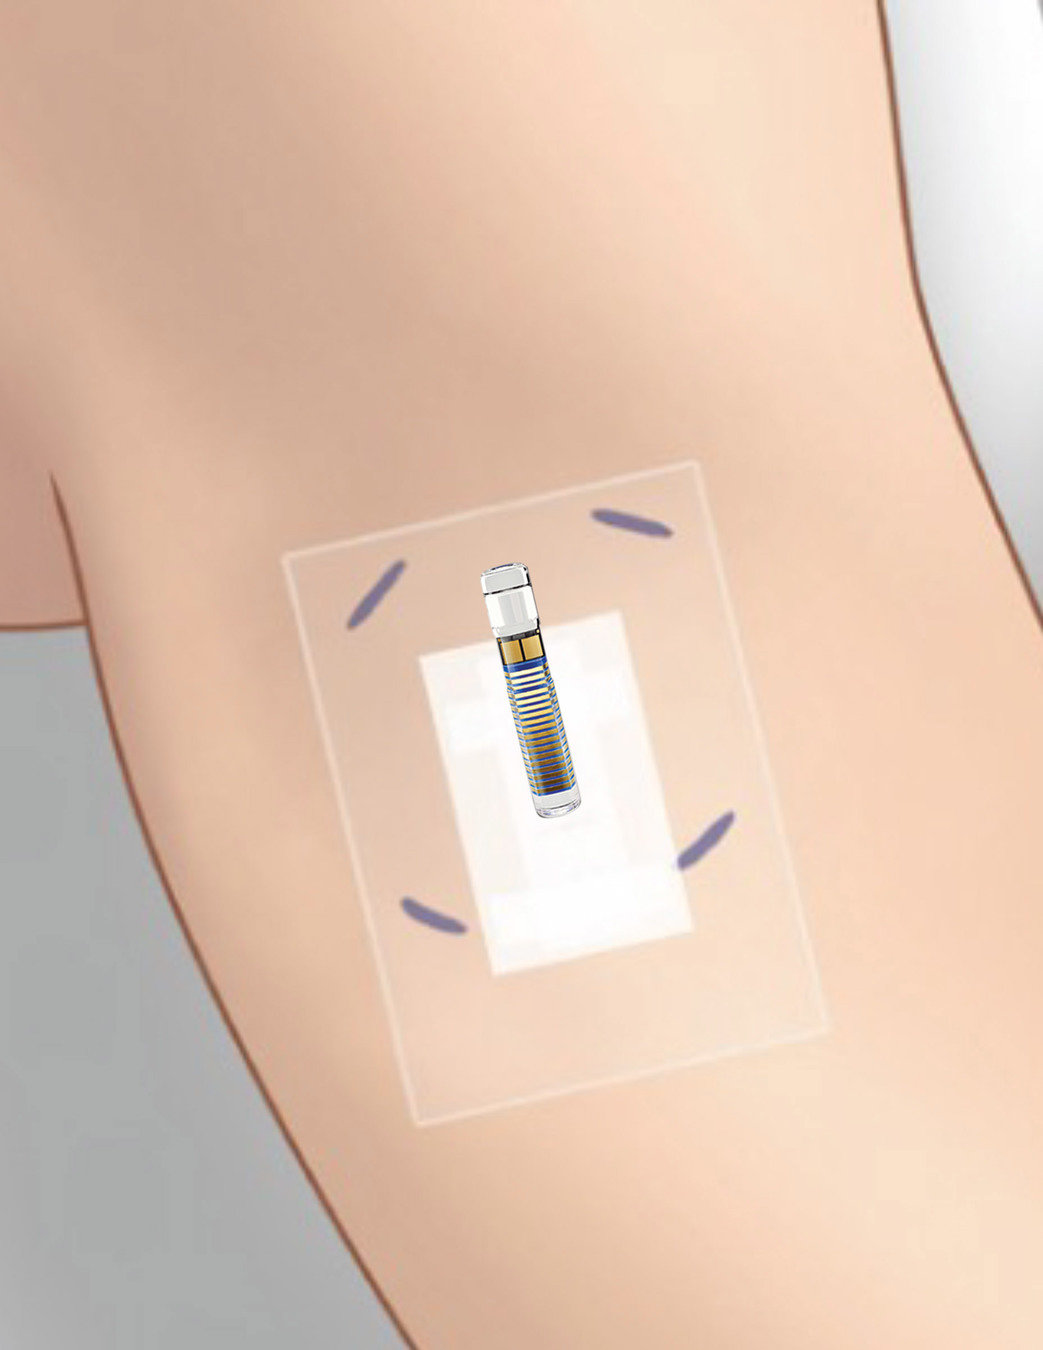

colocar el transmisor inteligente Eversense® E3 sobre el sensor Eversense® E3.

Si tiene una cinta de vendaje en el brazo, tendrá que quitársela para poder ver el apósito Tegaderm.

Es útil entender dónde está ubicado el sensor. El profesional de la salud ha introducido el sensor bajo la incisión, tal como se muestra aquí.

Esto quiere decir que es probable que el sensor esté debajo del centro del apósito Tegaderm.

También puede haber marcas visibles donde el profesional de la salud ha marcado las esquinas del transmisor inteligente antes de colocar el sensor. Alinear el transmisor inteligente en esta ubicación ayuda a colocarlo correctamente sobre el sensor.

Si lo necesita, mírese a un espejo para ver con claridad el apósito Tegaderm.

Sostenga el transmisor inteligente con el adhesivo como se muestra, con los lados del parche adhesivo hacia atrás. Si se pueden ver, utilice las marcas de las esquinas del transmisor inteligente que tiene en la piel para colocar el transmisor inteligente hacia la mitad superior del apósito Tegaderm.

Tenga en cuenta que el transmisor inteligente debe tocar el brazo.

Levante con suavidad y mueva ligeramente el transmisor inteligente junto con el adhesivo para encontrar la ubicación con la señal más fuerte, algún punto entre las 2-3 barras o de buena a excelente.

Puede ser de ayuda girar ligeramente el transmisor inteligente.